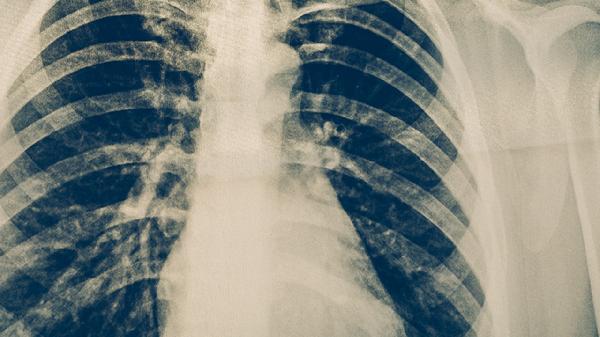

慢性阻塞性肺疾病是肺心病最常见的原因,长期吸烟或空气污染导致气道炎症和肺泡破坏,引起持续性气流受限。患者可能出现咳嗽、咳痰、活动后气促等症状。治疗需戒烟并使用布地奈德福莫特罗粉吸入剂、噻托溴铵粉雾剂等药物控制炎症,严重时需无创通气支持。

肺动脉压力持续升高会增加右心室负荷,长期可导致右心衰竭。可能与特发性肺动脉高压、结缔组织病相关血管病变有关,表现为呼吸困难、乏力、下肢水肿。医生可能建议使用安立生坦片、波生坦片等靶向药物,或进行房间隔造口术。

反复肺栓塞或血管炎可造成肺血管床减少,导致肺动脉阻力增加。患者可能出现咯血、胸痛、突发呼吸困难,需使用华法林钠片抗凝或行肺动脉取栓术。结缔组织病相关血管炎需联合泼尼松片免疫抑制治疗。